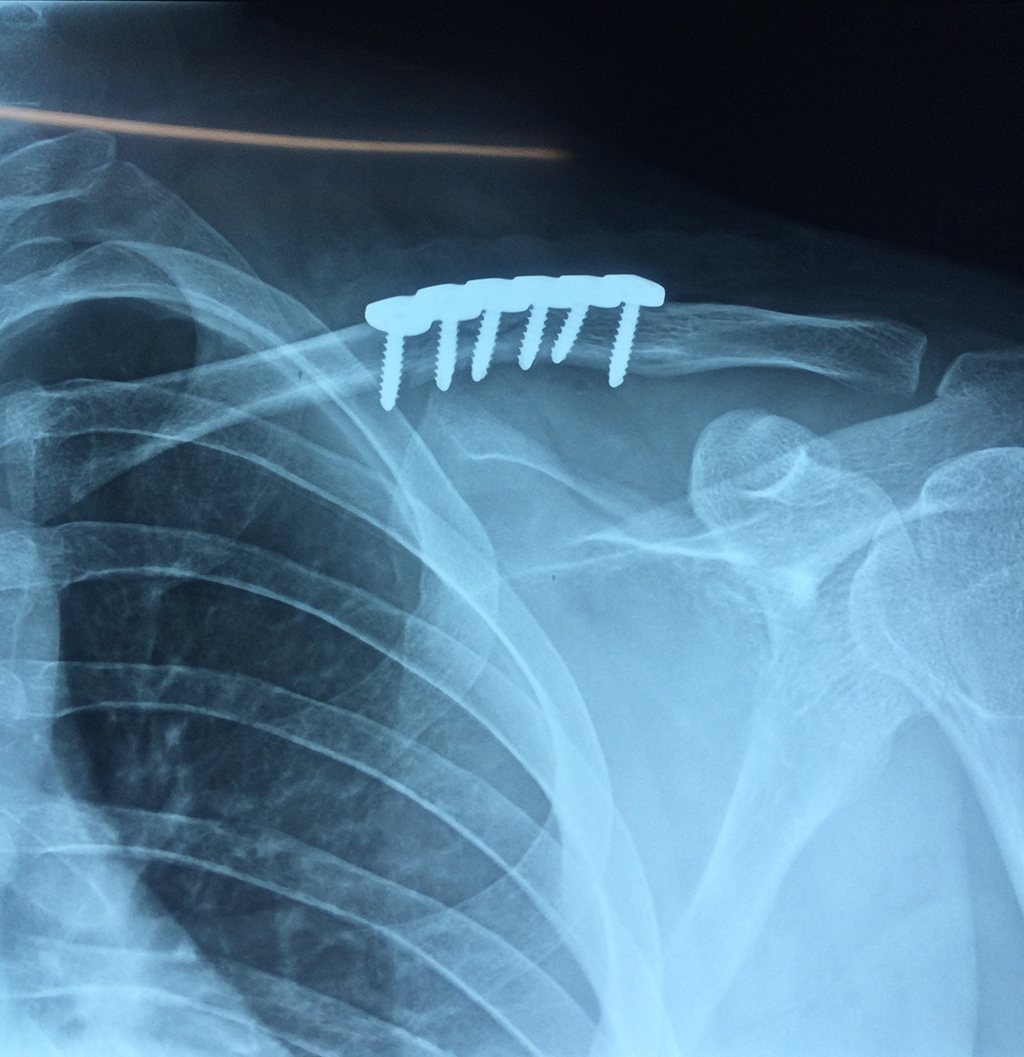

Clavicula 3

Detail Download